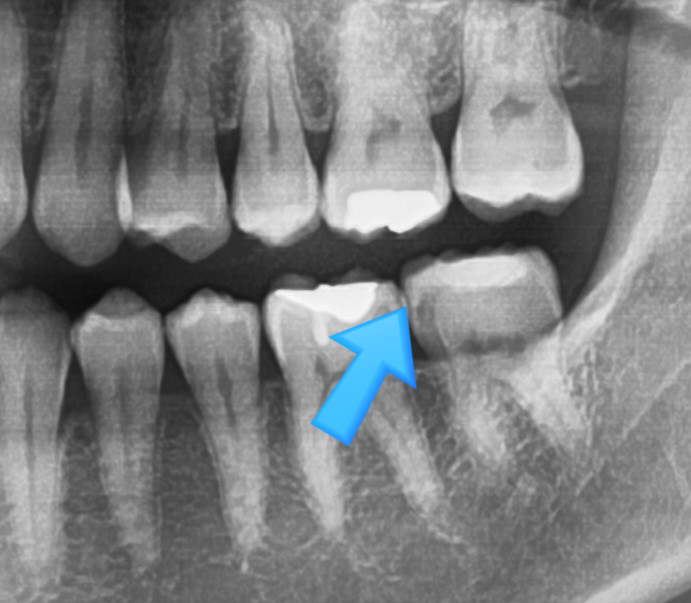

특히, 치아 속에 있는 충치는 눈으로는 보이지 않고, 엑스레이에서 볼 수 있는데요

오히려 이런 겉으로는 검게 보이지 않는 치아 속 충치가 더 위험합니다. 속에 위치하므로 더 깊기 때문이죠.

[아래 사진은 환자분이 공개에 동의한 사진입니다]

위 사진에서 치료가 필요한 충치가 보이시나요?

엑스레이에서는 명확히 알 수 있는데요

왼쪽처럼 겉에서는 멀쩡해보이는 치아도 파보면 충치가 있는 것을 확인할 수 있습니다.

위 사진에서 보듯이 왼쪽처럼 겉에서는 멀쩡해보이는 치아도 파보면 충치가 있는 것을 확인할 수 있습니다.